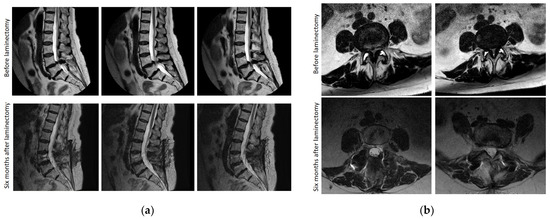

2.3.8. Magnetic Resonance Imaging Founds

3.8. Magnetic Resonance Imaging Examination